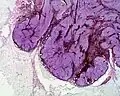

Histologie

Naevus bleu cellulaire